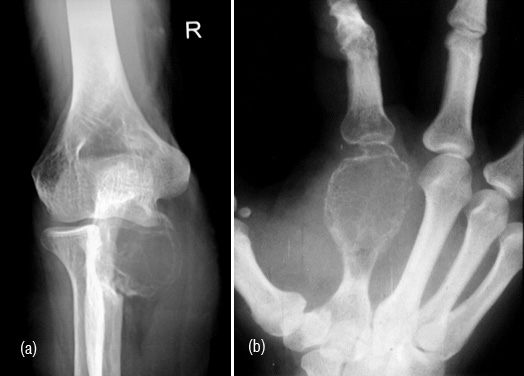

Brown tumor

Brown tumors (BT) are areas hemorrhage with fibroblasts and osteoclasts encoutered in hyperparathyroidism both in primary and secondary. These are cortically oriented osteolytic lesions occuring anywhere in the skeleton but common in long and flat bones (Figure 17a). Histiologically, resemble osteoclastoma (Figure 17b).

Figure 17: (a) Brown tumor in ulna, (b) Giant cell tumor.